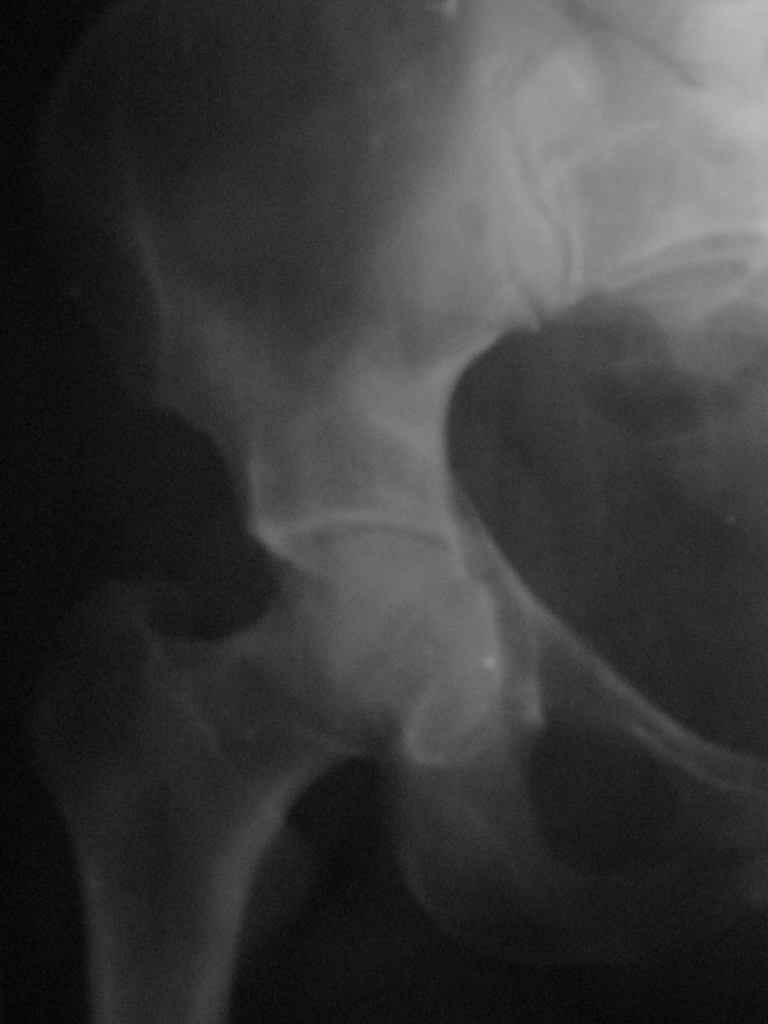

Женщина,58 лет, после ДТП 6 суток. Первично повреждение расценено как переломы ветвей лонной кости. После подтверждения повреждения вертлужной впадины,как чаще всего случается, вопрос встал о тактике. БОльшинство за консерватиное лечение.К сожалению кт у нас "во время" сломался. Прилагаю стандартные снимки вертлужки. У меня следующие вопросы к коллегам:1. Правильно ли рассценивать это повреждение как Т-образный перелом вертлужнй впадины?2. Можно ли добиться анатомической репозиции поверхности вертлужной впадины скелетным вытяжением в данном случае, если нет, что будет этому препятствовать?3. Если смещение останется таким как сейчас, через какое время появится необходимость эндопротезирования (по вашему опыту)?Спасибо.

Уважаемый Коваленко А.Н., снимки плохого качества и нет уверенности, что задняя колонна сломана (смещена). Если кт нет - везите больную в рентгенкабинет (палатником качественные снимки снимки не получатся) и сделайте обзорный снимок таза, Judet и может быть inlet, хуже вы ей не сделаете.